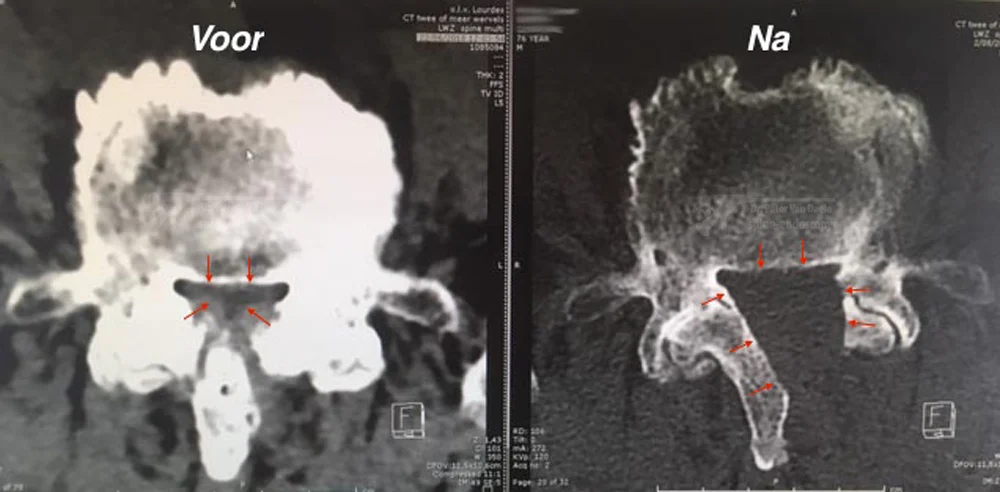

Hoe ziet een centraal kanaal na verbreding er op CT scan uit?

CT scan van L4-L5: linker foto toont zeer sterk vernauwd kanaal, rechter foto toont de bekomen ruimte winst met een full-endoscopische centraal kanaal verbreding (rode pijltjes markeren binnendiameter van het ruggenmerg kanaal)